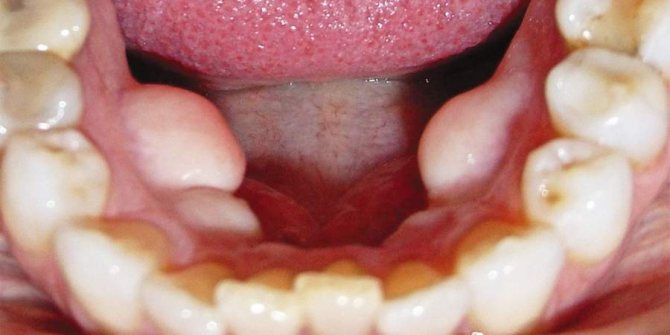

Экзостоз ротовой полости представляет собой разрастание костной и хрящевой ткани в определенном участке челюстного ряда. Визуально оно выглядит как шишка или узелок, который склонен к быстрому увеличению.

Острые края отвердевшей хрящевой ткани, формирующей экзостоз, могут повреждать покрывающую его слизистую оболочку, приводя к травмированию и возникновению сильной боли, затрудняющей процесс открытия ротовой полости и приема пищи.

На верхней челюсти экзостозные образования чаще всего локализуются в области жевательных элементов с внешней или внутренней стороны ряды. При поражении нижней челюсти наросты формируются у основания резцов, клыков и премоляров.

- на десне прослеживается бугорок, покрытый слизистой оболочкой, которая может выглядеть неизмененной либо покрыться мелкими шипами;

- нарост увеличивается в размере и из горошины может превратиться в крупную шишку, которая вызывает дискомфорт и мешает полноценному расположению языка;

- слизистая оболочка постепенно приобретает насыщенный розовый оттенок;